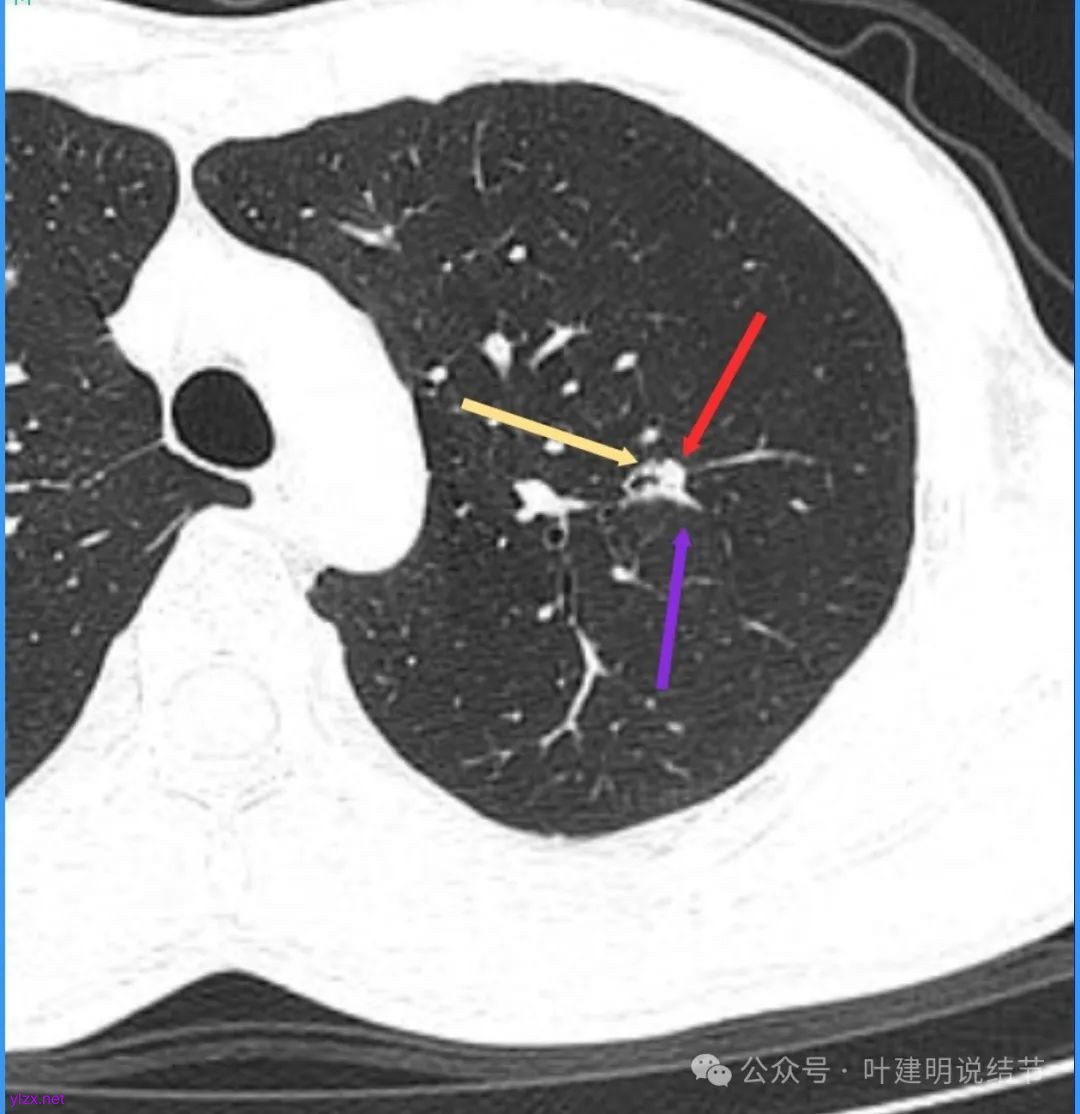

再看看近半年前2024年11月时的影像:

我们发现一是病灶与25年3月的几乎没有区别,二是原来蓝色箭头处不太像血管,而是结节边缘的一部分,而结节灶内又是有扩张支气管的。

左肺上叶这个病灶总体上来讲2025年3月的与2024年11月份相比没有显著进展。我们逐层从细节上去分析,会发现:1、病灶开始出现的层面就有临近的支气管扭曲变形,这些人用肿瘤导致的牵拉不能解释,反而用细支气管扩张伴慢性炎容易解释;2、病灶内部仍然多个层面都有见到扩张的细支气管,可是如果是肿瘤,与导致细支气管扩张相应的病灶本身的收缩力或者边缘毛刺又不明显;3、病灶边缘基本上都比较光滑平直,没有像外周浸润性生长的枫叶或者毛刺;4、虽然有血管贴边或者进入,但是说不上显著的血管异常增粗;5、整体来讲病灶实性成分密度过高,随访对比进展不明显,用结节是恶性不太能够解释相应的影像表现,所以我倾向于考虑是细支气管扩张伴有周围慢性炎或者肉芽肿性炎。至少从风险高低的角度来看,几个月的间隔没有明显进展的情况下加上位置又不好,如果手术需要切除范围比较多,所以应该在随访观察比较稳妥,可以考虑半年复查对比。意见供参考!